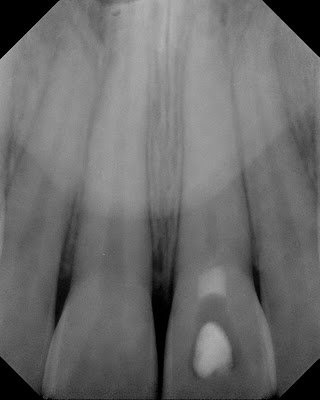

This 13 year old boy previously suffered a traumatic injury. Tooth #8 has discolored. The tooth is asymptomatic. Non-responsive to thermal testing, normal to percussion and probing.

Partial pulpal obliteration is noted. A 1mm thick calcific barrier is found just below the level of the CEJ

CT is initiated and a complete calcific barrier is noted. It was decided to perform the internal bleaching without endodontic therapy.